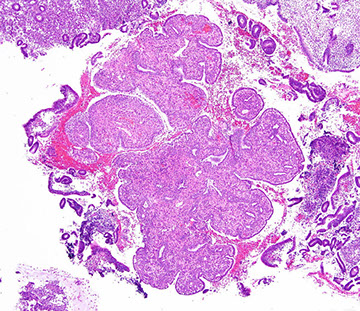

Lobular Endocervical Glandular Hyperplasia

Rare, women of reproductive age mostly asymptomatic or c discharge, mass or abdominal discomfort

- may be assoc c Peutz-Jeghers

Micro: well-defined border of lesion c distinct lobular prolif of round variably-sized glands lined by simple mucin-producing columnar cells c bland basal nuclei usually in bottom 1/2 of cervical wall and sometimes surrounded by inflam

- can appear slightly atypical and have up to 2 mits / 10 hpf

IHC: (+) MUC6, HIK 1083, scattered chromogranin A and SYN

- neg: ER/PR, CEA

DDx: minimal deviation adenoca: has haphazard arrangement of glands c more variability in nuclei, and extends further through cervical wall and has desmoplastic rxn and sometimes vascular invasion (should not rely on IHC to make dx)